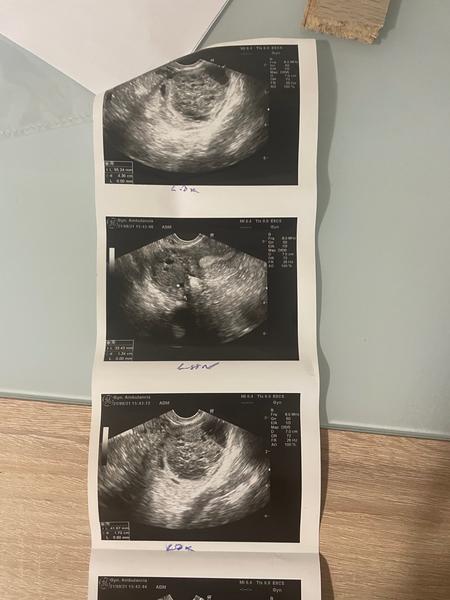

Aký problém je vidieť na fotkách zo sona?

mám 23 rokov a o dieťa sa snažíme dva mesiace. Doktorka ma poslala do CAR. Zatiaľ mi nebola nasadená žiadna liečba. Menštruačný cyklus mám 30 - 33 dňový.

USG bol spravený na 19. deň cyklu, krvné výsledky sú v poriadku.

Čo je vidieť na fotkách zo sona?

pri UZV vyšetrení vieme posúdiť ako vyzerá uterus, ovaria, či prítomné patológie v oblasti dutiny uteru, vajíčkovodov a ovárií.